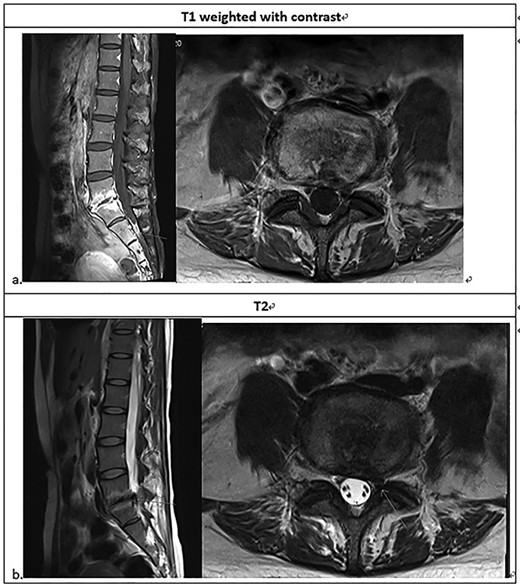

Lumbarsacral spine MRI (a) posterior bulging disc at L5-S1; extruding disc at the left subarticular zone of the left L5-S1, with compression of the left S1 nerve root; neural foraminal stenosis at left L5-S1; increased enhancement at L5-S1 related to the spondylitis change; (b) The arrow point at neural foraminal stenosis at left L5-S1.

She was referred to our institute for spine consultation at 3 months after surgery. On physical examination, she had numbness at the left S1 dermatome and saddle anesthesia. Visual analog scale was 8 when admission. The straight leg raising test was bilaterally negative. She had no lower extremity weakness. Contrast-enhanced lumbar-spine MRI showed posterior bulging disc with decreased disc space and endplate changes of L5-S1. We suspected an extruding disc in the left subarticular zone at left L5-S1, compressing the left S1 nerve root. There was increased enhancement at L5-S1, but the paraspinal soft tissue was clear without enhancement (Fig. 1).